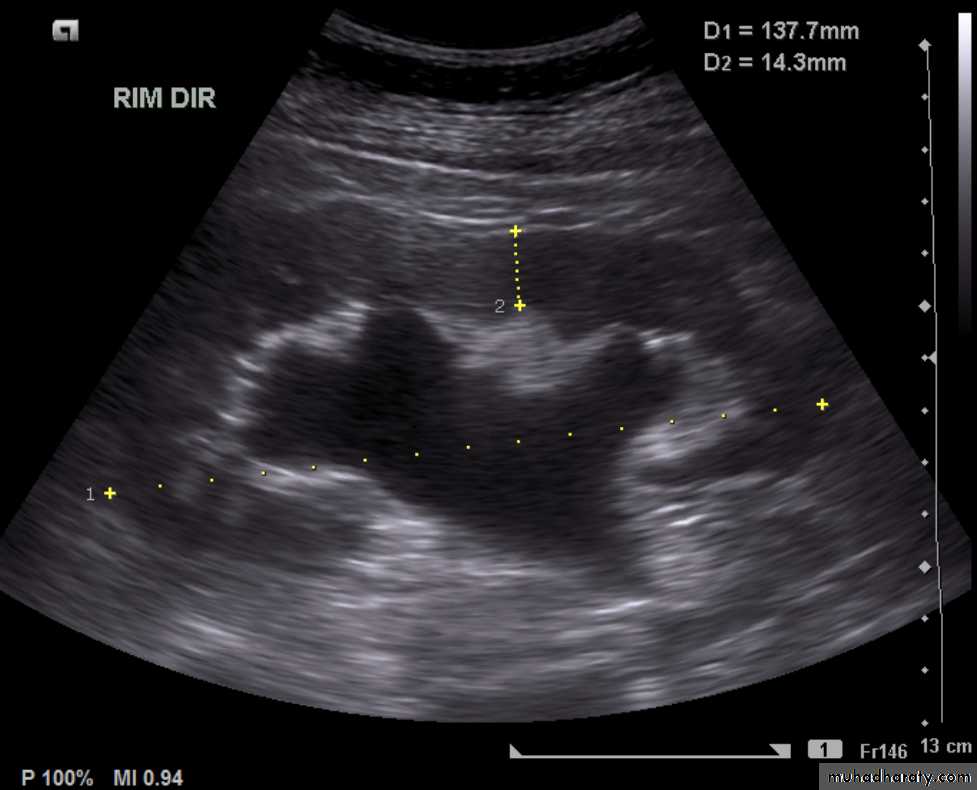

hydronephrosis